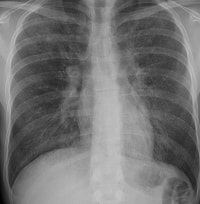

肺障害

リウマチでは、

間質性肺炎、

肺線維症がみられることがあり、これらはリウマトイド肺とよばれています。自覚症状としては、息切れ、空咳などがあります。ただ、メトトレキサートをはじめとする抗リウマチ薬の副作用でも間質性肺炎をおこすことがありますので、どちらの原因でおこったのかを見極めることが、治療上大変重要になります。

肺に水がたまる胸膜炎をおこすこともあります。さらに、まれですが、 閉塞性器質性細気管 支肺炎(BOOP)といわれる移動性の肺炎をおこすこともあります。